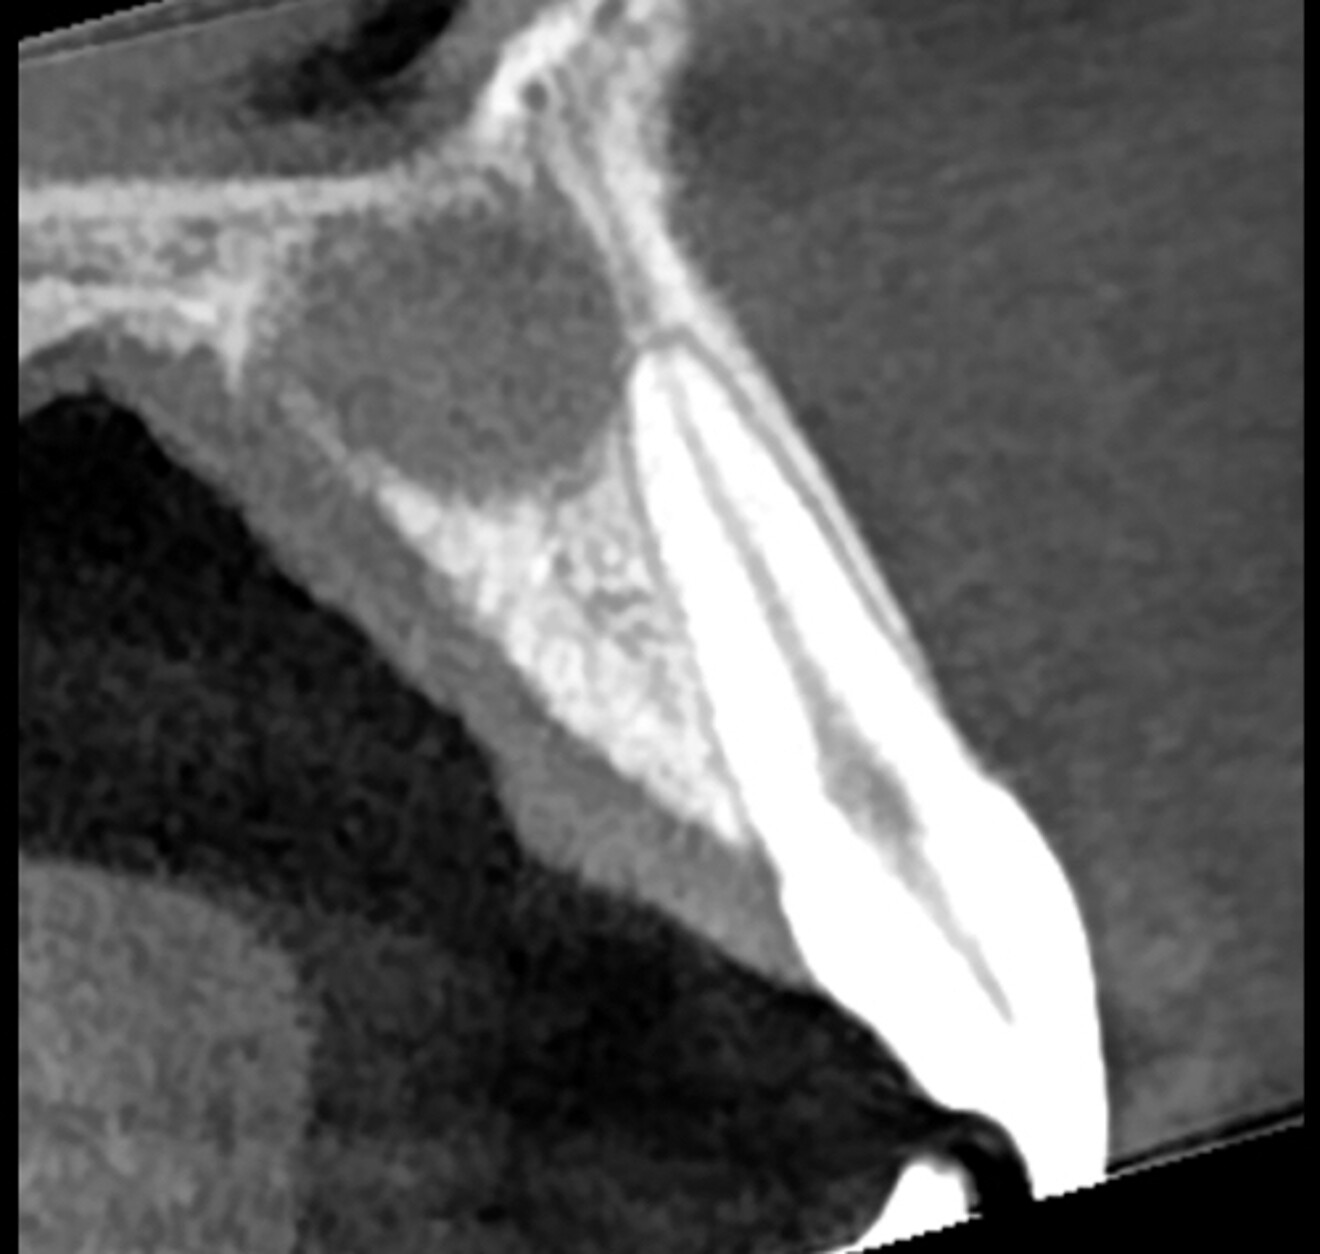

At the two-year follow-up appointment, the radiograph showed healing, but there appeared to be a superimposed image at the apex (Fig. 5). A high-definition CBCT scan taken with the DEXIS OP 3D showed that this was not a lesion but fibrous tissue consistent with physiological healing from the palatal area where the cortical plate had been largely damaged (Fig. 6). Since this was not pathological but a normal reparative process, there was no need to interfere.

Fig. 6: High-definition CBCT scan with the DEXIS OP 3D showing fibrous tissue above the root.